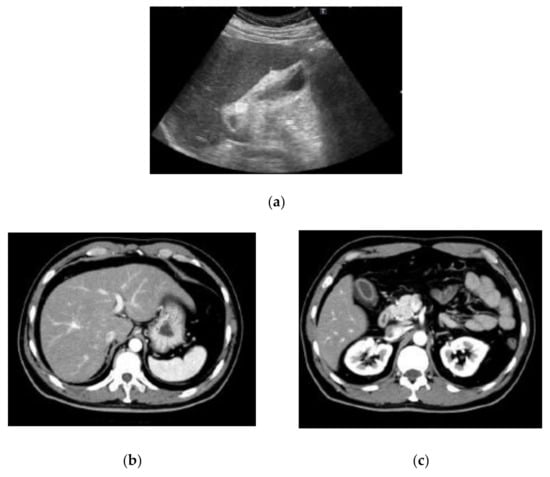

The laboratory data on admission are listed in Table 1. Liver dysfunction was observed in addition to severe transaminase levels. Hepatitis viral markers and autoantibodies were negative. Thyroid function was within normal limits: thyroid stimulating hormone, 1.66 μIU/mL; free tri-iodothyronine, 3.25 pg/mL; and free thyroxine, 1.49 ng/dL. We also performed a drug lymphocyte stimulation test (DLST). DLST was positive for benzbromarone (stimulation index (SI), 561%), Hyakusosan (SI, 406%), and bilastine (SI, 403%). These drugs were provided by this patient. On the DLST, the drug at 0.1, 1 or 10-fold of maximum plasma concentration was added to the lymphocytes separated from our patient’s plasma. Lymphocytes were cultured for 72 h, and 3H-thymidine was then added [14]. After culturing the lymphocytes for 16–18 h, radioactivity resulting from the uptake of 3H-thymidine was measured by the cells during deoxyribonucleic acid (DNA) synthesis in counts per minutes (cpm). The SI was calculated as the ratio of proliferation (cpm) with the drug/proliferation (cpm) without the drug [14]. Abdominal ultrasound, computed tomography and magnetic resonance imaging results indicated acute liver injury (Figure 1). We did not observe any signatures of chronic hepatitis or cirrhosis.

Figure 1.

Findings of abdominal ultrasound (US) (a), computed tomography (CT) (b,c) and magnetic resonance imaging (MRI) (d,e) examinations. US indicated acute liver injury with thickening of the gall bladder wall and minimal ascites on the underside of the liver (a). The contrast-enhanced CT scan also indicated acute liver injury with thickening of the gall bladder wall (b,c). MRI indicated acute liver injury with periportal abnormal intensity (d) and thickening of the gall bladder wall (e).